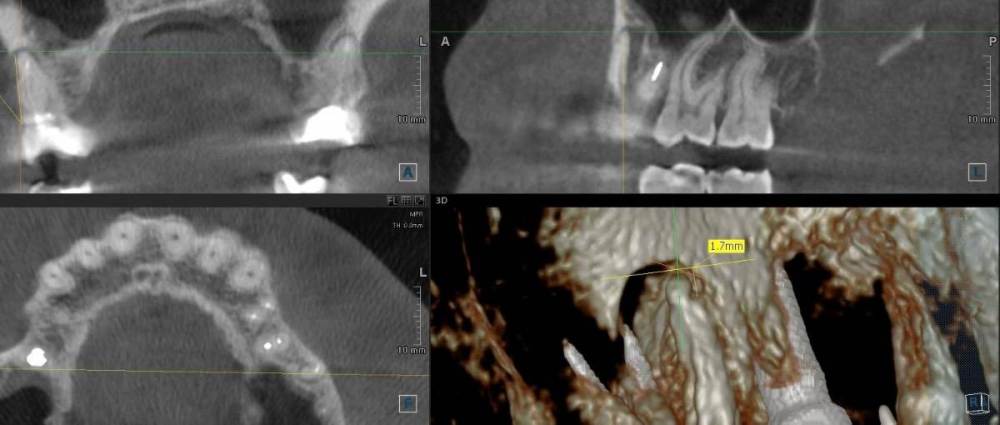

ict Опубликовано 22 июня, 2021 Автор Поделиться Опубликовано 22 июня, 2021 (изменено) изначально пломбировалось вероятно резорцином, каналы вскрывались с трудом, легко прошло ультразвуком. Никак не беспокоило, редко незаметные ощущения типа почесывания при жевании. Пломба была с краю плоха, поэтому решил поменять. При вскрытии проблемного канала было подтекание крови, что насторожило врача, подумал что перфорировал корень. На неделю временно оставил под временной пломбой, зуб никак не беспокоил. Так как по рентгену не смог ничего увидеть (что канал нормально пройден), то запломбировал (второй снимок в первом посте) триоксидентом (первый снимок в первом посте), сверху жидкотекучий композит и оставил под временной пломбой. Промывал 0.5%, а не 3% раствором. Нашел еще снимок 2019 года, киста на 0.1 мм выросла за год по сравнению со снимком 2018г. (линию провел). Сейчас думаю оставить так и поставить постоянную пломбу или имеет смысл снова вскрыть и что-то делать. Прикрепил снимок от 2019 года Изменено 22 июня, 2021 пользователем ict Ссылка на комментарий

ict Опубликовано 24 июня, 2021 Автор Поделиться Опубликовано 24 июня, 2021 не стал выскрывать, поставил постоянную пломбу обычный снимок с инстументом видел, по нему ничего не видно - прямая. По воспоминаниям врача до конца не прошел, возможно склерозирован. Гноя, жидкости не было, только кровь. Возможно поступала из ответвления (на срезе можно заметить). Осенью сделаю кт, посмотрю что с гранулемой Ссылка на комментарий